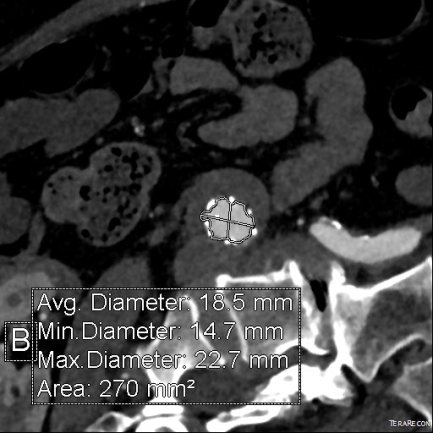

For example, take this patient who after EVAR of aortic aneurysm with AFX developed metachronous dilatation of the common iliac artery to 3.9cm with abdominal pain. The average diameter is 18.5mm. From the table, that rounds to 19mm corresponding to 283.53 square mm. If the internal iliac artery requires a 13mm graft, that is 132.73 square mm, the difference being 150.80 square mm. That corresponds to a 14mm diameter graft, but a slightly larger graft is preferred for oversizing. The external iliac artery is 8mm, and putting a 13mm Viabahn (largest available) in that would result in the B-infolding in the 8mm external iliac. Here, I bailed myself out by simply placing a 20mm AFX iliac limb extension, which by virtue of its design is resistent to infolding and tolerant of parallel grafts laid alongside in constricted channels. I found that the AFX iliac limb, a 20-13mm x 88mm length extension well suited for this.